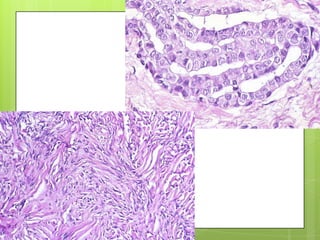

PATOGENIA

 Fibras de asbesto en bronquiolos

respiratorios y alveolos producen una

reaccion. Macrofagos fagocitan y

eliminan fibras cortas, pero no fibras de

mayor longitud (fagocitosis incompleta)

se liberan enzimas lisosomicas y material

fibrinógeno soluble.